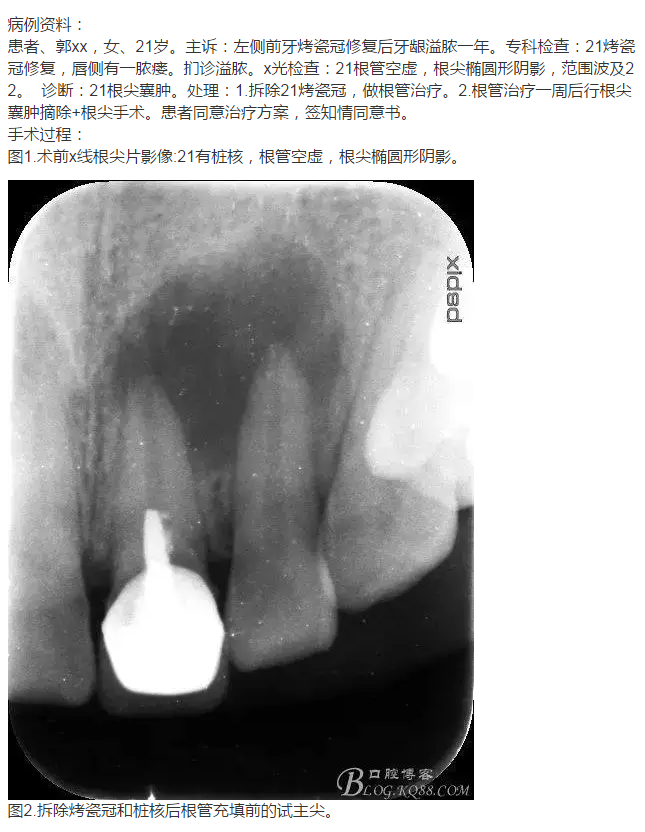

轉:張東星 愛齒-KQ88口腔醫(yī)學